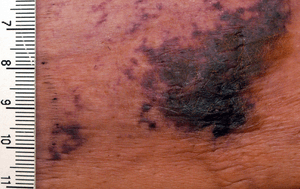

Calciphylaxis on the abdomen of a patient with end stage renal disease. Markings are in cm. | |

The first skin changes in calciphylaxis lesions are mottling of the skin and induration in a livedo reticularis pattern. As tissue thrombosis and infarction occurs, a black, leathery eschar in an ulcer with adherent black slough are found. Surrounding the ulcers is usually a plate-like area of indurated skin.[3] These lesions are always extremely painful and most often occur on the lower extremities, abdomen, buttocks, and penis. Because the tissue has infarcted, wound healing seldom occurs, and ulcers are more likely to become secondarily infected. Many cases of calciphylaxis end with systemic bacterial infection and death.[1]

There is no diagnostic test for calciphylaxis. The diagnosis is a clinical one. The characteristic lesions are the ischemic skin lesions (usually with areas of skin necrosis). The necrotic skin lesions (i.e. the dying or already dead skin areas) typically appear as violaceous (dark bluish purple) lesions and/or completely black leathery lesions. They can be extensive. The suspected diagnosis can be supported by a skin biopsy. It shows arterial calcification and occlusion in the absence of vasculitis. Sometimes the bone scintigraphy can show increased tracer accumulation in the soft tissues.[7] In certain patients, anti-nuclear antibody may play a role.[8]